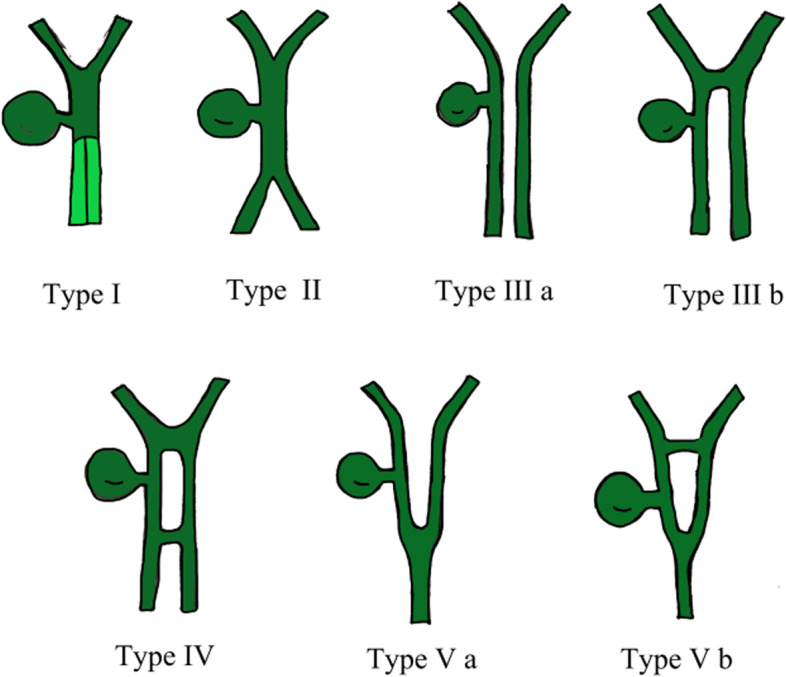

Duplication of the common bile duct is an extremely rare condition. The presence of double bile ducts is a normal step in human early embryogenesis. The definite lumen of the bile tree is developed by epithelial proliferation and vacuolization. As the vacuoles coalesce, they will initially create two parallel channels, which will gradually recede to form an isolated common anatomical structure of the common bile duct [ref. 4]. Regression failure of the double biliary system is considered to be the mechanism of type I anomaly [ref. 5].Chance elongation and early subdivision of the primitive hepatic furrow may be responsible for the other types of DCBD [ref. 6].The latest classification system of the DCBD proposed by Choi et al. [ref. 7] (2007) based on morphology which did not take into account of the aberrant CBD exits. They described five subtypes involving seven variants (Fig. 3). Since then, three new variants of double common bile duct were reported consecutively, however, none of these were classified into classification system [ref. 8–ref. 11] (Fig. 4). Our case is a new variant of diaphragmatic common bile duct duplication type I.The reason that why our case was classified as type I was that it was confirmed intraoperatively that there was a septum in common bile duct rather than two separate common bile ducts. The septum of original type I was located in the common bile duct. In our case, the septum in the common bile duct extended to the junction of the left and right hepatic ducts. The above-mentioned variants need a comprehensive classification to encompass these newly discovered variants. Thus, our classification system is as follows (Fig. 5): Type I, Partially (a) or completely (b) septum within the lumen; Type II, the distal bile duct bifurcates to two independent drainages; Type III, double biliary drainage without any communication (a), with intrahepatic communication (b); Type IV, double biliary drainage with extrahepatic communicating channels; TypeV, duplicated commen bile ducts join as a single biliary drainage channel,the gallbladder is attached to the repeated biliary ducts or Left or right hepatic duct (a), the gallbladder is connected to the common bile duct before or after separation(b). Our classification is including all types of common bile duct duplication reported in the present literature. Because of the location of the gallbladder junction and the location of the traffic between the repeated biliary ducts, our classification may contain additional variations not found.